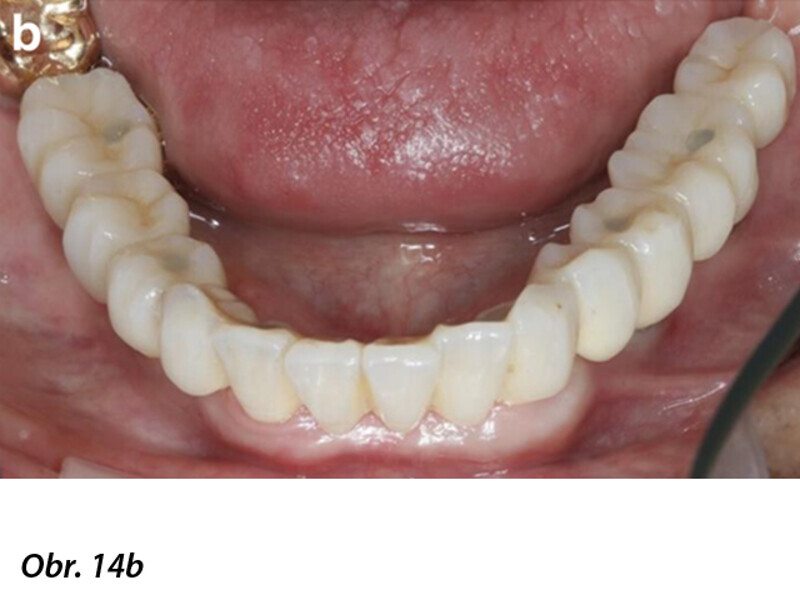

Počítačem asistované, šablonou se řídící okamžité zavedení a zatížení implantátu v dolní čelisti